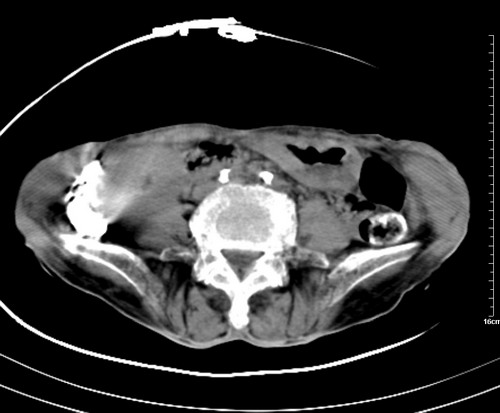

病人,女,79岁,主要因腹疼二月入院,彩超,肝,胆,脾,未见异常,胸透上消化道造影未见异常,化验白细胞增高,内科医生让做胸部ct检查,因为熟人多做了腹部(外科会诊考虑胆囊炎).现ct片如下请假各位战友.

1 气管旁、隆突下淋巴结明显肿大,肝左叶外侧段低密影,都考虑转移。

2 肝右后叶下段明显增大,片状低密影,但因各种伪影显示不佳,不排除病变。

后中纵隔团块影,伴气管、食道受压移位,首先考虑转移瘤,肝s5段低密度灶。建议增强检查,另外其结肠是否有问题请提供,右肺部分肺叶局限含气增多,考虑局限肺气肿。